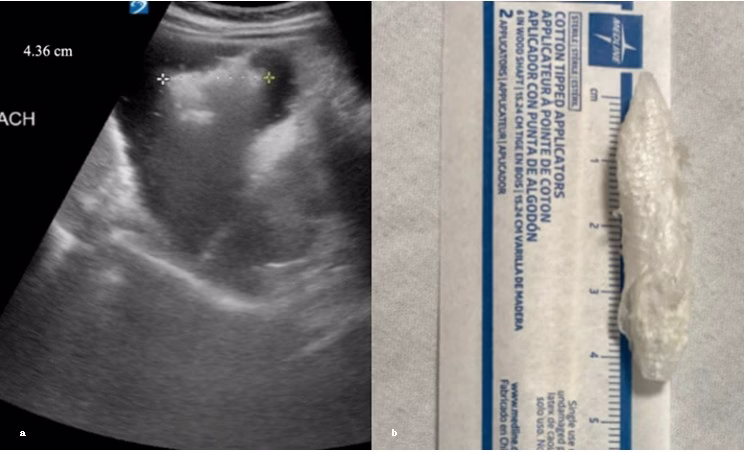

A healthy 8-year-old boy presented with his mother with concern of possibly swallowing a plastic bottle cap. The ingestion was unwitnessed, making it uncertain whether the patient had swallowed anything; therefore, a gastric POCUS evaluation was performed to investigate further. POCUS was initially inconclusive due to lack of gastric dilation and mixed contents. We asked the patient to drink water, which further distended the stomach while providing a better medium for visualization. He also assumed a left lateral decubitus position to shift the bowel gas away. With the patient lying on his left side, a curvilinear probe was placed in the transverse plane over the epigastric area and we scanned the region until the stomach was identified. POCUS revealed a hyperechoic object with irregular and jagged margins within the anechoic lumen of the stomach, measuring 4.36 cm (Figure 3a). Notable dirty shadowing and reverberation artifacts were present, consistent with the acoustic properties of plastic. In Figure 3b, the patient’s mother displayed an identical bottle cap—approximately 4.3 cm in size—that her son had been chewing, confirming foreign body ingestion. With this confirmation, the pediatric gastroenterologist advised outpatient surgery follow-up within 1-2 weeks and strict return precautions. During a follow-up call, the mother confirmed that the patient expelled the bottle cap within seven days without experiencing any complications, indicating a complete and uneventful recovery.

Figure 3. Figure 3a reveals a hyperechoic object with irregular and jagged margins within the anechoic lumen of the stomach, measuring 4.36 cm. Figure 3b displays an identical bottle cap that the patient was chewing on, also measuring 4.36 cm.

In our second case, gastric ultrasound following water ingestion and patient repositioning revealed a 4.36 cm hyperechoic foreign body, later confirmed to be a chewed bottle cap. This observation supports findings by Yamamoto et al. (2017), who demonstrated that strategic positional changes can enhance gastric ultrasound by helping foreign bodies float into view—an easily implemented technique requiring minimal additional training [11]. Horowitz et al. 2016 reported that POCUS identified gastric foreign bodies in three pediatric cases [12]. Two of these were confirmed with standard radiographs, while the third, not identified radiographically, was passed in the feces. All three objects were initially found in the stomach using POCUS. These studies reinforce the value of POCUS as a reliable, noninvasive diagnostic tool. Our patient successfully passed the bottle cap without complications, requiring no additional imaging or interventions, demonstrating the usefulness of POCUS in safely guiding conservative treatment and avoiding unnecessary radiation exposure. Broader adoption among frontline providers could significantly reduce dependence on radiography, decrease pediatric radiation exposure, and facilitate faster, safer clinical decision-making.